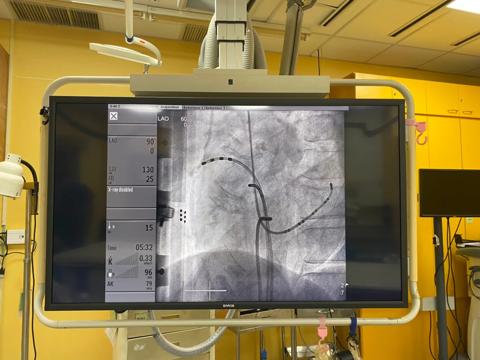

Barco’s Nexxis IVR solution met their quality requirements and was installed at the end of June 2020. Its large display system enabled a neater and more simplified operation environment for the care team. The simplified interventional workflow, in turn, improved the efficiency of the operating suite. The MDSC-8358 replaced 6 individual displays with 1 in the exam room, while the MDSC-8231 replaced 4 individual displays with 1 in the control room of the Cath lab.

Choosing Barco as their trusted solution partner, the Cath lab was able to derive accurate color images with ultra-low latency and reduced noise, making real-time critical imaging more specific. Surgical displays MDSC-8358 and MDSC-8231 introduced intuitive user interfaces with dynamic and flexible layouts. Seamless views from multiple sources in the exam room enabled medical practitioners to drive more effective operational outcomes.